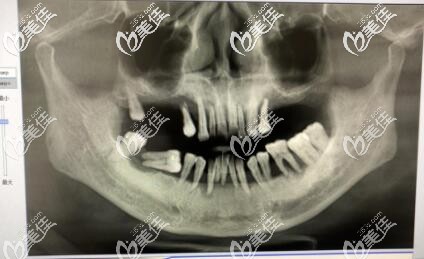

美奧口腔不斷引進的齒科設(shè)備和技術(shù),在種植牙和牙齒矯正方面實力雄厚,是疑難種植數(shù)字化研究,士卓曼種植修復(fù)教學(xué)基地。

美奧口腔牙齒種植不一味推薦貴的種植體,會充分結(jié)合顧客口腔結(jié)構(gòu)、骨質(zhì)特點以及身體耐受力定制專屬于個人的口腔種植體系放心,針對牙槽骨條件差老年人種牙,院內(nèi)開展 All-on-4即刻種植牙,不僅大大節(jié)省了費用,而且創(chuàng)傷更小,更快,讓老年人少受罪快速種牙。